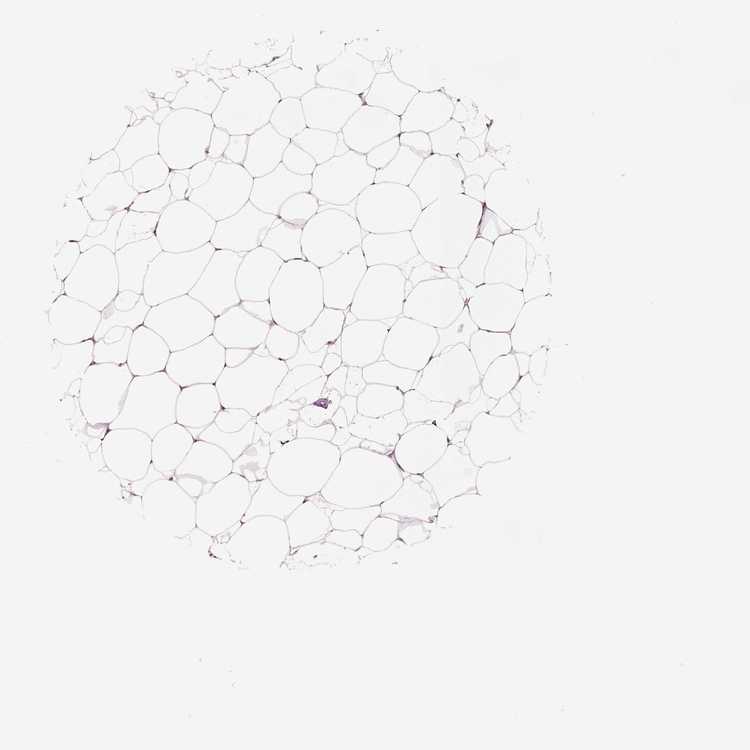

BREAST - Antibody stainingi

Antibody staining in the annotated cell types in the current human tissue is reported as not detected, low, medium, or high, based on conventional immunohistochemistry profiling in selected tissues. This score is based on the combination of the staining intensity and fraction of stained cells.

Each image is clickable and will lead to virtual microscopy that enables deeper exploration of all samples and also displays staining intensity scores, fraction scores and subcellular localization as well as patient and tissue information for each sample.

Antibody HPA001648Antibody HPA005631Antibody HPA059585

Adipocytes Not detectedNot detectedMedium

Glandular cells MediumMediumMedium

Myoepithelial cells LowMediumMedium